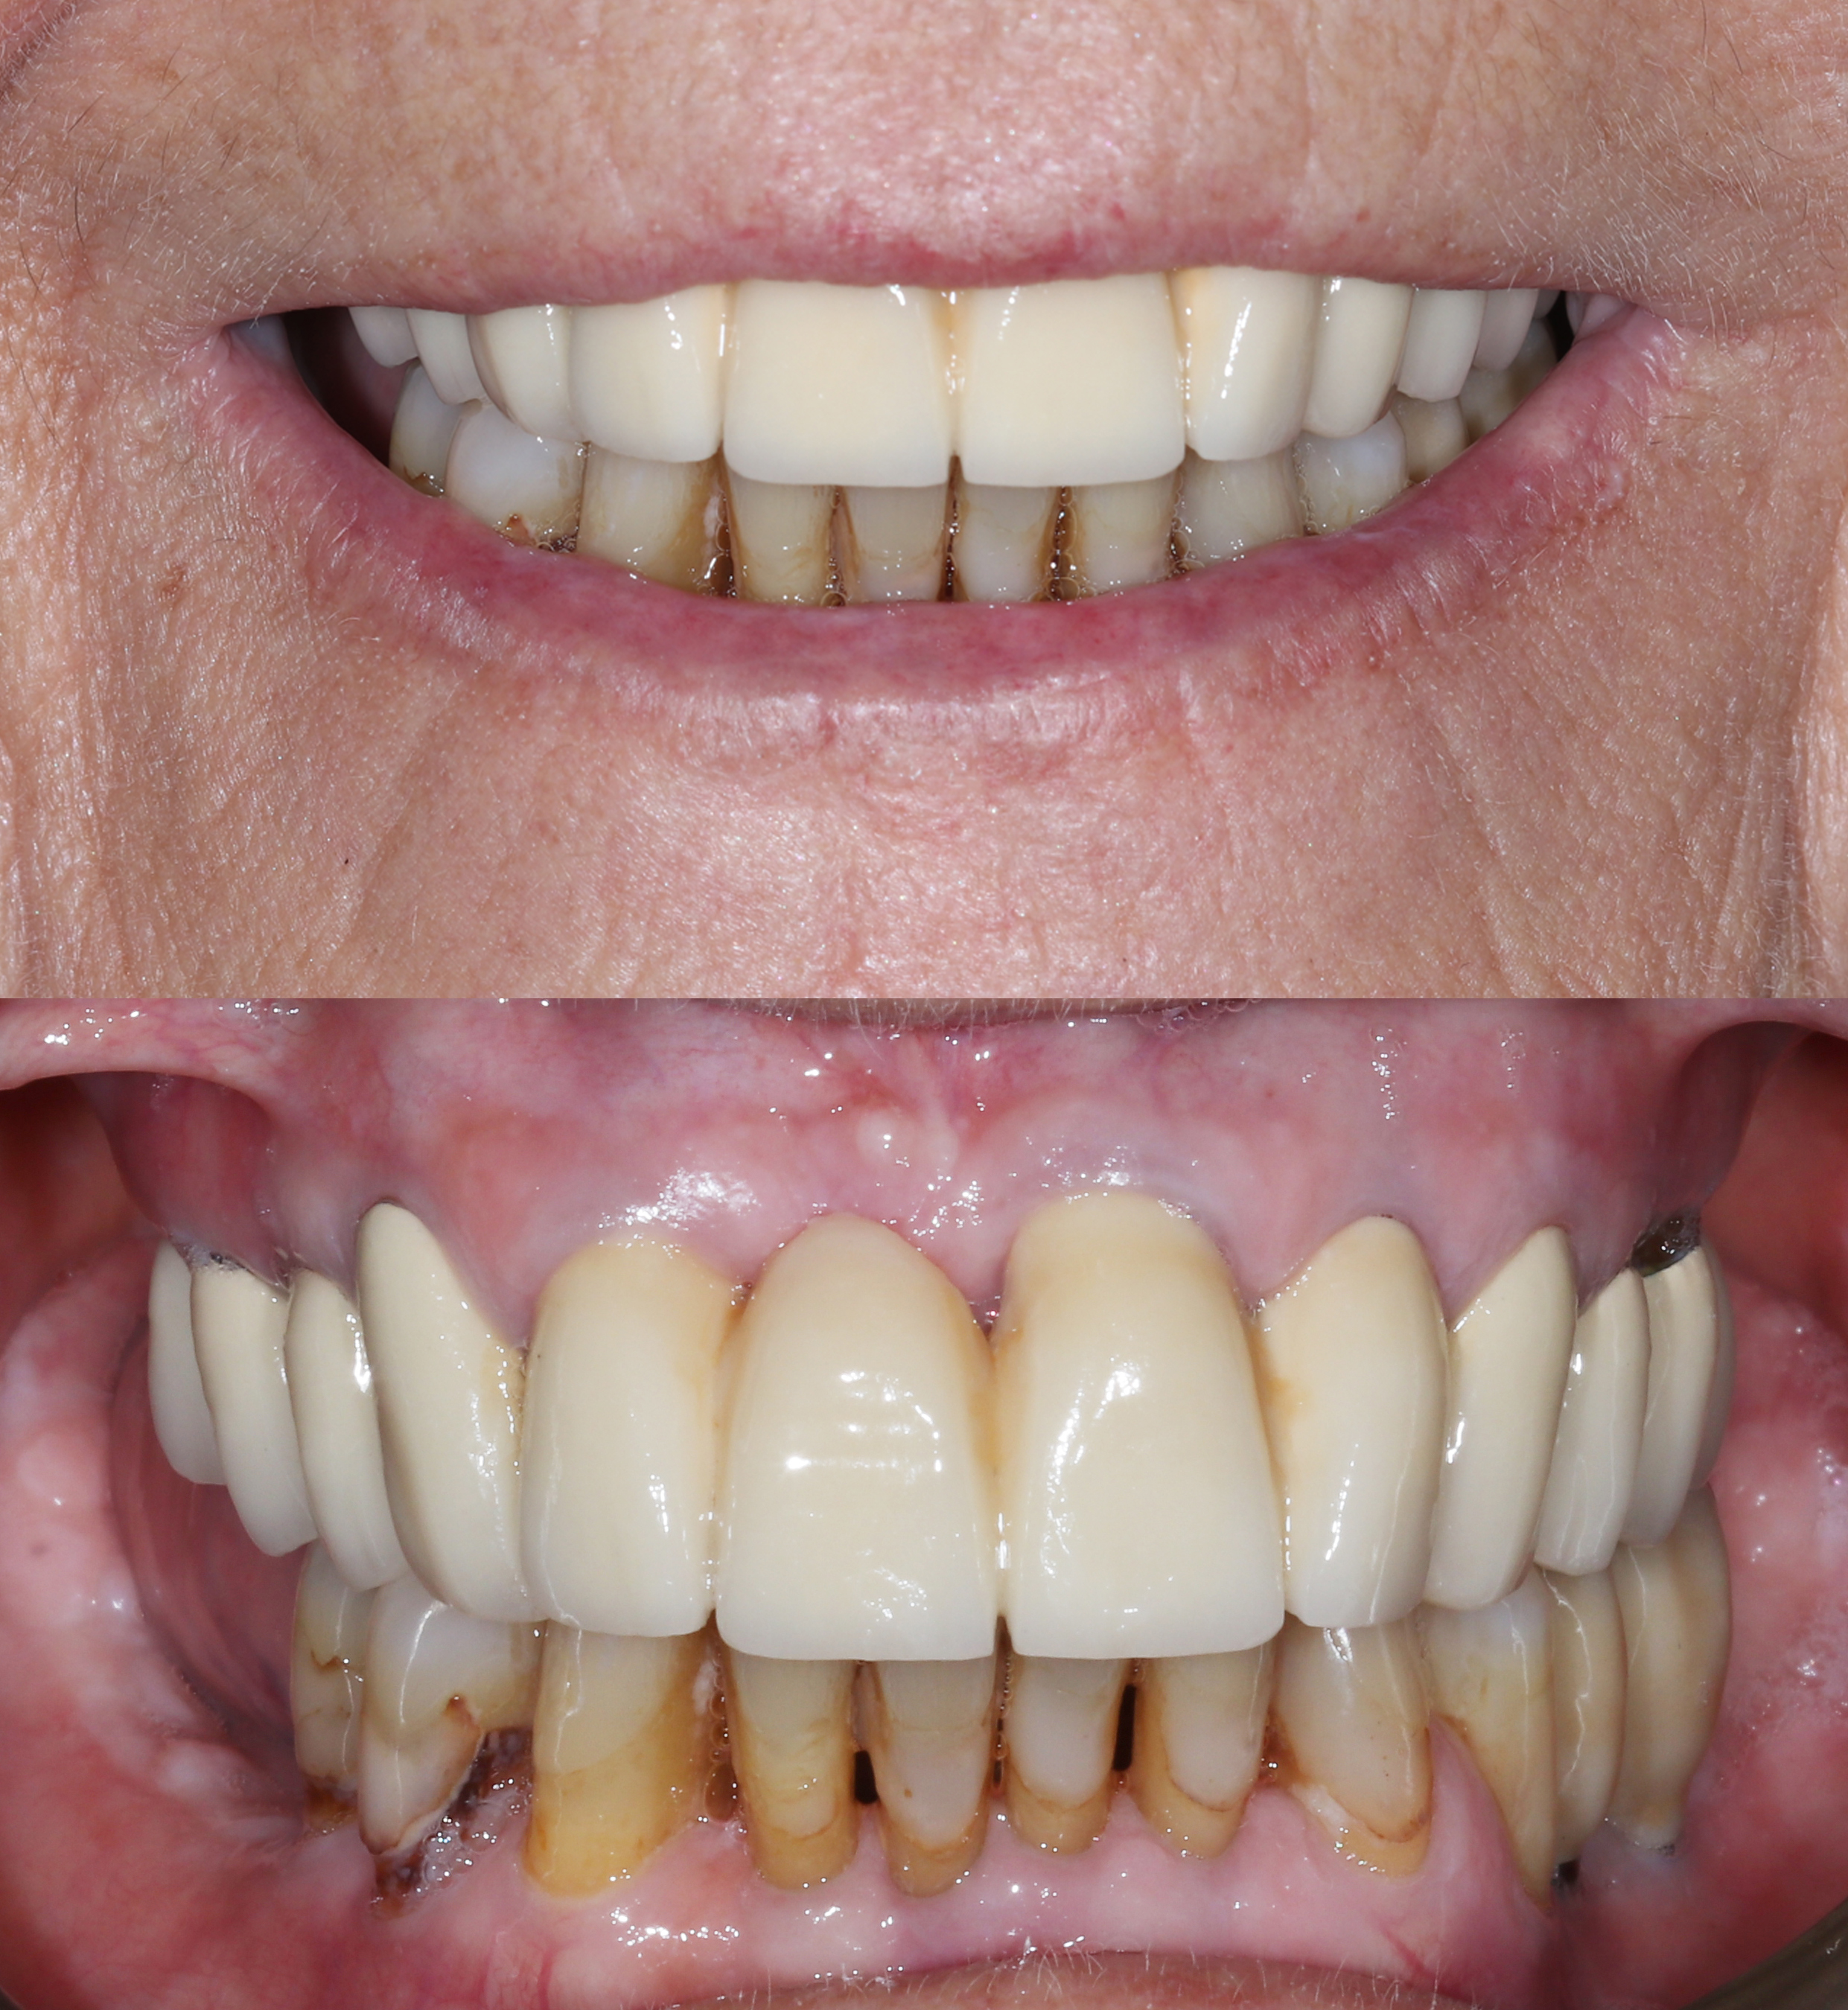

Αρχική κατάσταση - Χαμόγελο και πρόσθια άποψη

Αρχική κατάσταση - Πλάγια άποψη